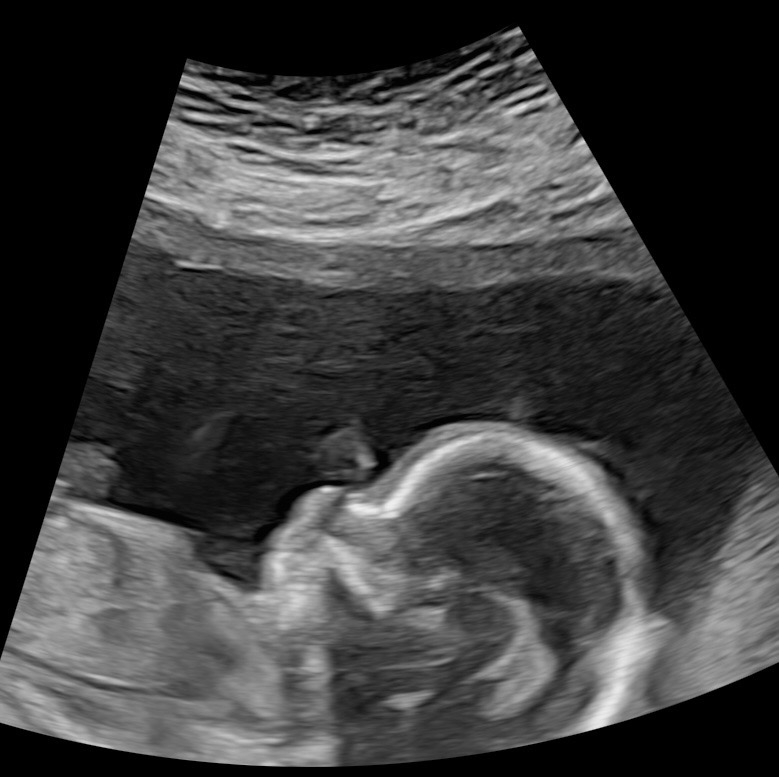

Sophie and Noah Banks are expecting another little girl…Marigold! During the anatomy scan they found out she has spina bifida myelomeningocele, the most severe form of spina bifida. This means as her spine was forming, her back did not close properly and her spinal nerves are outside of her body and being damaged by amniotic fluid, which they learned has also caused both of her feet to be clubbed. As of now her brain looks “normal” with little to no fluid seen in there…typically this isn’t the case. Right now (11/10/25) they are waiting to find out if they qualify for fetoscopic surgery to prevent more damage being done to her & repair her back. Surgery will require Sophie to stay months in Houston before birth & afterwards for NICU care. If she doesn’t get the surgery, Sophie will have to deliver either in Houston or Little Rock to have neurosurgeons & other specialized doctors near, which will also include a 4-6week stay before birth & NICU stay afterwards.